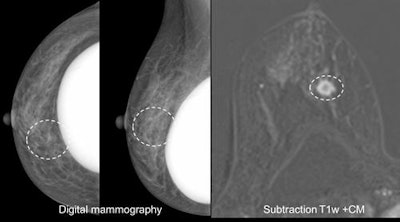

Case 3: A 51-year-old woman with discharge on the left side and a suspected papilloma on the left side. Problem-solving MRI revealed a carcinoma on the right side BI-RADS 5 that was missed both by mammography and ultrasound.The issues surrounding equipment needed for wider routine use of breast MRI will also differ across Europe, according to Baltzer. In Austria, as in Hungary, Slovakia, and Italy, a proportionally higher number of scanners or examinations per population compared with other member states, translates into MR exams that are half the cost of those performed elsewhere, such as in Germany.